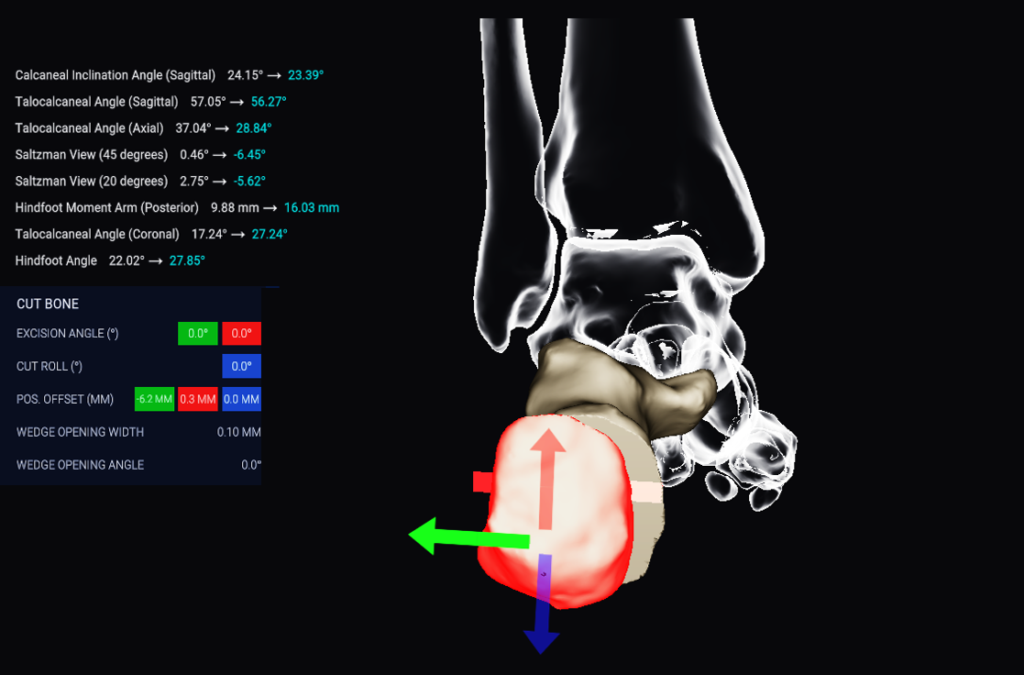

Automatic analysis of radiographic parameters, that support you in quantifying dislocations, deformities and suspected impingement

Excellent applicability for various diagnoses of the hindfoot and forefoot e.g., progressive collapse flat foot deformity and post-traumatic osteoarthritis